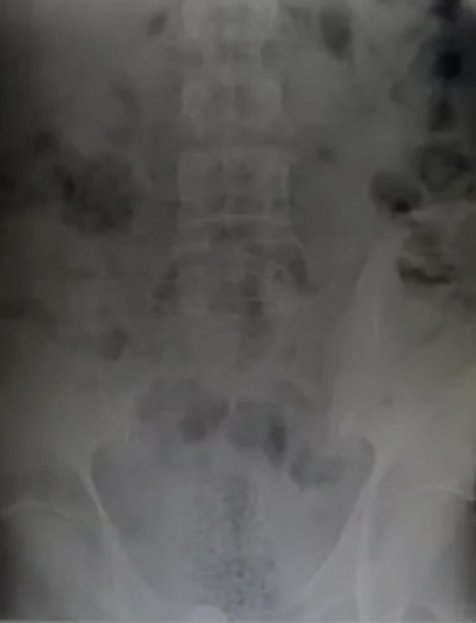

El hombre se negó a someterse a un examen médico para confirmar la presencia de un objeto extraño en su cuerpo. Un agente del equipo de Investigaciones de Seguridad Nacional llegó y un agente especial de HSI obtuvo una orden de registro poco después de la medianoche del 1 de abril, lo que permitió al personal médico de un hospital local tomarle una radiografía y realizarle un examen.

La radiografía confirmó la presencia de un objeto extraño oculto en el interior. Los agentes de la CBP continuaron vigilando al hombre mientras recibía atención médica, y finalmente expulsó un paquete justo antes de las 2 p. m.